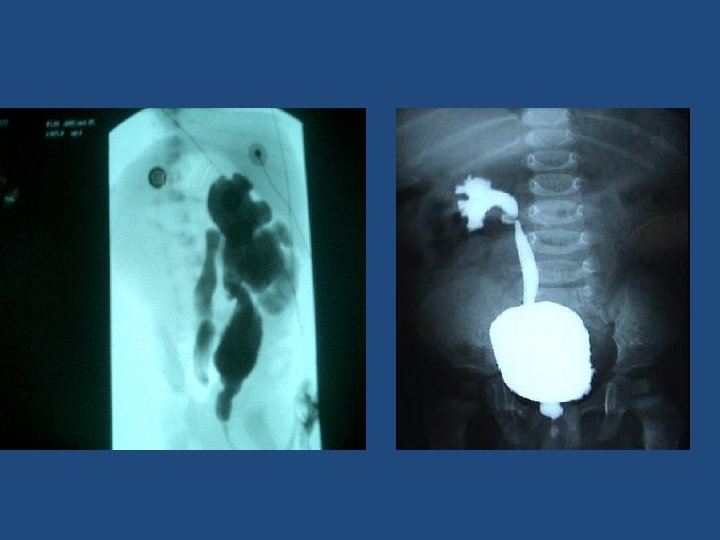

• In our experience the surgical indications consist of grade 4 and 5 VUR. The lower grades are usually controlateral VUR. In these cases surgery, especially the “Cohen” technique, gives a definitive correction of the reflux (98%). • The cost of STING technique for bilateral VUR using Deflux is the same as the cost of surgery, with a relapse rate as high as 45% in high grades VUR. • Usually parents prefer a radical correction of VUR…

Transtrigonal ureteral reimplantation (Cohen)